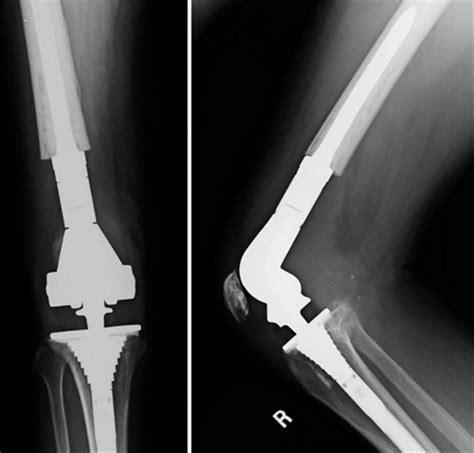

• Total Joint Replacement: This involves replacing the entire joint with an artificial implant. Common examples include total hip replacement and total knee replacement.

• Surgery: The surgical procedure involves making an incision to access the joint, removing the damaged bone and cartilage, and replacing it with an artificial implant. The type of implant used depends on the specific joint and the extent of the damage.

• Robotic-Assisted Surgery: Robotic systems provide surgeons with greater precision and control during the procedure, resulting in more accurate implant placement.

• Custom Implants: Advances in 3D printing and imaging technologies allow for the creation of custom implants tailored to the patient’s unique anatomy.